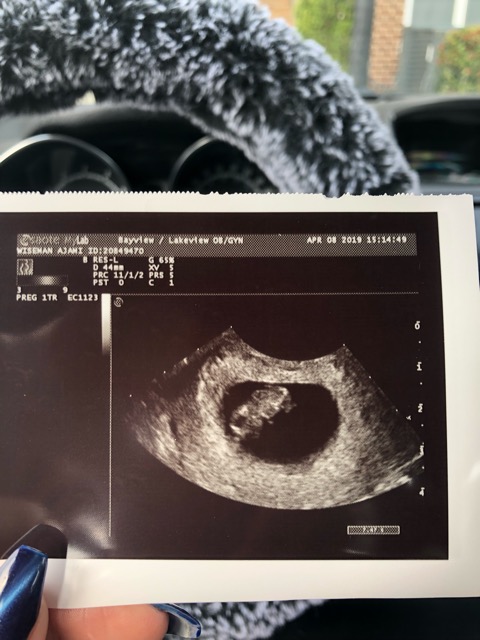

Baby looks bigger than predicted date..

I recently switched to a new OB and based on dates she believes I’m 7 weeks and 5 days. Based off a private ultrasound I went to I’m supposedly 8 weeks. I know it’s a few days different but a lot of people have been saying my ultrasound picture looks like a baby bigger that 8 weeks? What do you think? This is my first pregnancy so I have nothing to compare it to, does baby look bigger than 8 weeks?